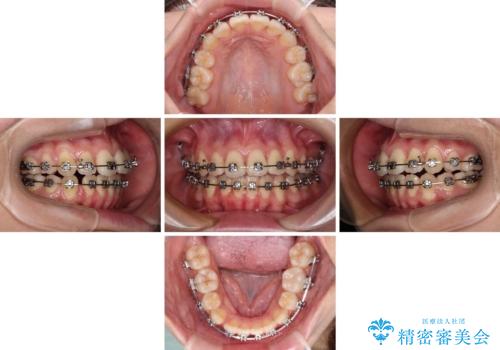

- メタルブラケット

- 1年6ヶ月

- 抜歯矯正の後戻りを気にして来院された患者様です。

舌の突出癖によるオープンバイトになっていたため、インビザラインによるマウスピース矯正をおすすめしましたが、自己管理の自信がないとのことで、ワイヤー装置による矯正治療を行うこととしました。

舌の突出癖が認められると、上下前歯の隙間を閉じることができません。

舌のトレーニングをしっかりと行っていただくことで、歯列を整えることができます。